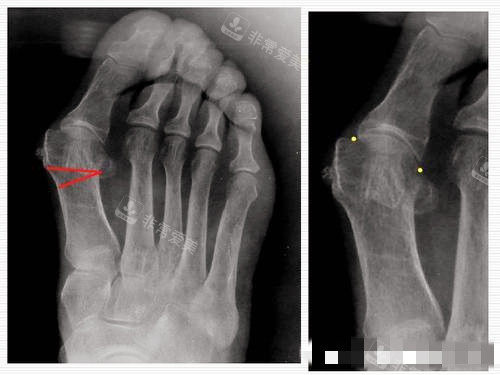

大脚骨对比图

大脚骨脚步骨头透视图

大脚骨X光片图片